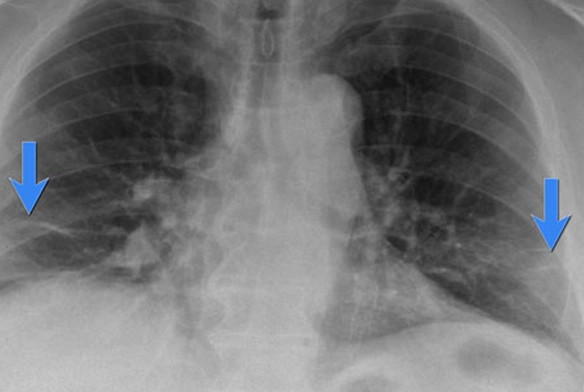

آب آوردن ریه در سالمندان، یا ادم ریوی، به تجمع غیرطبیعی مایعات در ریهها گفته میشود که موجب اختلال در تبادل اکسیژن میشود و در نتیجه باعث مشکلات تنفسی جدی میگردد. این وضعیت اغلب در افرادی رخ میدهد که مشکلات قلبی یا کلیوی دارند، اما میتواند به دلایل دیگری نیز ایجاد شود. در سالمندان، به دلیل ضعیفتر بودن سیستمهای بدنی و مستعد بودن به عوارض ناشی از بیماریها، احتمال بروز این مشکل بیشتر است. این مشکل، اگر به موقع تشخیص داده نشود، میتواند به مشکلات جدیتر مانند نارسایی تنفسی و حتی مرگ منجر شود. درمانهای فوری و مراقبتهای پزشکی برای مدیریت این شرایط ضروری هستند.

یکی از شایعترین دلایل آب آوردن ریه در سالمندان، نارسایی قلبی است. نارسایی قلبی زمانی رخ میدهد که قلب قادر به پمپاژ خون کافی به بدن نیست. این مشکل باعث میشود فشار در رگهای خونی ریه افزایش یابد و در نهایت مایعات به ریهها نشت کنند. این وضعیت معمولاً در افراد مسنی که دچار نارسایی قلبی مزمن هستند مشاهده میشود. علاوه بر نارسایی قلبی، مشکلاتی مانند دریچههای آسیب دیده یا تنگشده قلب نیز میتواند باعث نشت مایعات به ریهها شود.

سایر دلایل شامل بیماریهای ریوی مانند ذاتالریه و یا مشکلات کلیوی است. در این موارد، ریهها به دلیل عفونت یا نارسایی کلیه مایع اضافی را نگه میدارند و این مایع به داخل ریهها نشت میکند. افزایش فشار خون نیز میتواند به طور ناگهانی باعث ادم ریوی شود. در برخی از سالمندان، عفونتهای شدید یا مشکلات کلیوی منجر به تورم و تجمع مایعات در بدن و در نهایت در ریهها میشود. این وضعیت نیاز به پیگیری و درمان دقیق دارد تا از بروز عوارض جدیتر جلوگیری شود.

یکی از مهمترین علائم ادم ریوی در سالمندان، تنگی نفس است. این مشکل به ویژه هنگام دراز کشیدن بیشتر میشود و ممکن است باعث بیدار شدن شبانه سالمند به دلیل احساس خفگی و نیاز به نشستن شود. در برخی موارد، سالمندان ممکن است دچار خسخس یا سرفههای خشک و شدید شوند. این علائم نشاندهنده تلاش بدن برای به دست آوردن اکسیژن بیشتر و از بین بردن مایعات اضافی در ریههاست.

تورم در پاها و افزایش سریع وزن نیز از علائم دیگر ادم ریوی است. این تورم به دلیل تجمع مایعات در بدن ایجاد میشود و ممکن است به تدریج گسترش یابد. همچنین، سالمندان ممکن است خستگی شدیدی را تجربه کنند که ناشی از ناتوانی ریهها در تبادل اکسیژن و حذف مایعات اضافی است.